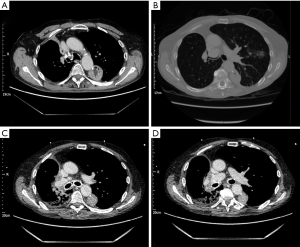

There is no consensus on the optimal treatment of post-lobectomy bronchial kinking with evidence of treatment of symptomatic patients limited to case reports. Endobronchial stenting has been successfully employed in a small number of patients (44,45). Figure 1 shows kinking following right upper lobectomy in a patient at our institution who had previously undergone oesophagectomy. The patient was severely symptomatic with breathlessness and stridor. Temporary stenting was undertaken with benefit. Where stenosis is severe with collapse or where torsion cannot be excluded, re-exploration with VATS should be the first line to exclude torsion and facilitate repositioning of the lobe, bronchopexy to the pericardium and repair of inferior pulmonary ligament which may provide symptomatic improvement (34).